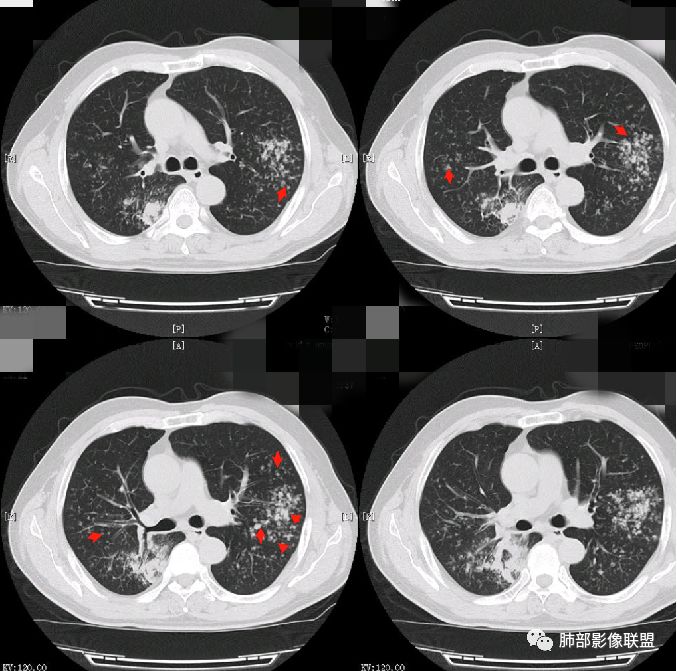

病灶的形态与分布如何?

多发实变影,呈叶段分布,形态及密度都比较单一,比较柔和

病灶的走形如何?                                                                                                以外围胸膜下分布为主,长轴与胸膜平行

病灶的边缘如何:

大部分边缘膨隆,局部边缘稍收缩

病灶内的支气管如何:                                                                            支气管走形通畅自然,部分于近端堵塞,管壁光整

病灶内的坏死如何?:                                                                                             病灶内有坏死空洞,大部分空洞内壁光整,部分空洞内少许分隔影,呈“鬼脸”样空洞

周围情况如何?:                                                                                                   周围肺野有模糊晕,未见明显树芽征,与胸膜有糊墙改变

患者临床轻影像重,CRP增高,社区获得性肺炎常规不考虑,年轻人,不是许多机会性感染的易感人群,特殊性感染性病变有结核和隐球,但是结核形态多发,好发于上叶及下叶背段,密度不均一,通常有树芽,而且结核空洞呈虫蚀样且内壁光整,不作为首先考虑病灶形态单一,有晕征,有空洞及空洞内分隔,病灶分布与胸膜平行,隐球比较符合,但是结核影像多样化,年轻人,也需要临床进一步检查除外结核。    病例为什么不首先考虑OP或淋巴瘤,病灶内支气管情况有助于判别,OP收缩性往往很强,所以病灶内支气管应该稍扩张而且没有堵塞,淋巴瘤起源于支气管粘膜下和肺间质,往往沿血管支气管束方向分布,与胸膜垂直为主,病灶内支气管壁增厚并直达远段,易合并支气管扩张;年轻人肺炎型肺癌少见,而且影像表现也不支持,如果患者治疗效果不好,需要临床进一步检查排查肺癌。